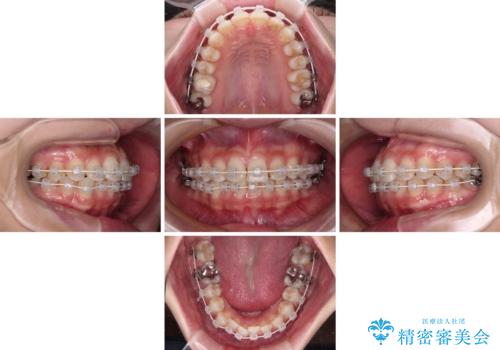

- 歯並びと虫歯をきれいにしたいとのことで来院された患者様です。

楽して短期間で歯列を整えたいとのことで、ワイヤー装置を用いて矯正治療を行い、矯正治療後に下顎の虫歯はセラミックインレー、上顎はPGAインレー(ゴールドインレー)、根管治療を行う歯についてはオールセラミッククラウンにて補綴治療を行うこととしました。

矯正治療は8ヶ月ほどで終了し、速やかに虫歯治療に移行することができました。

保険治療で用いる樹脂(コンポジットレジン)で行った虫歯治療は、周辺が変色して汚くなっていましたが、下顎はセラミックインレーで審美的に、上顎はPGAインレーで歯に負担の少ない治療を行うことができました。